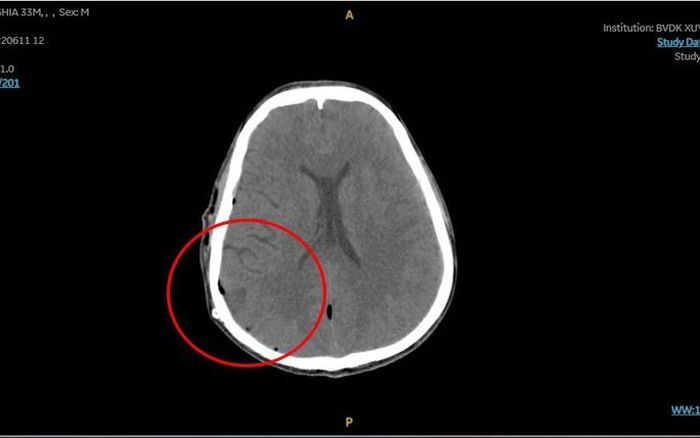

Khối máu tụ khi vào viện gây chèn ép não. Ảnh: BVCC

Ê-kip cấp cứu lập tức đưa anh N. vào chụp CT, kết quả cho thấy sọ có đường nứt nhẹ, xuất huyết não do đứt một mạch máu nhỏ vì chấn thương. Bệnh nhân được đưa vào phòng mổ để cầm máu, hút máu tụ khoảng 150 ml.

Khối máu tụ đã được lấy đi hoàn toàn và cầm máu, Ảnh:BVCC